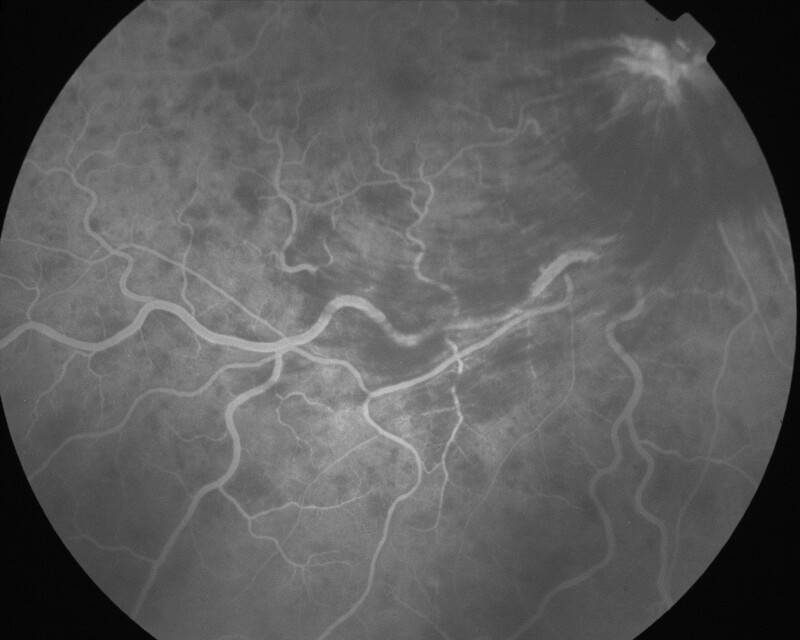

IMG0018.jpg